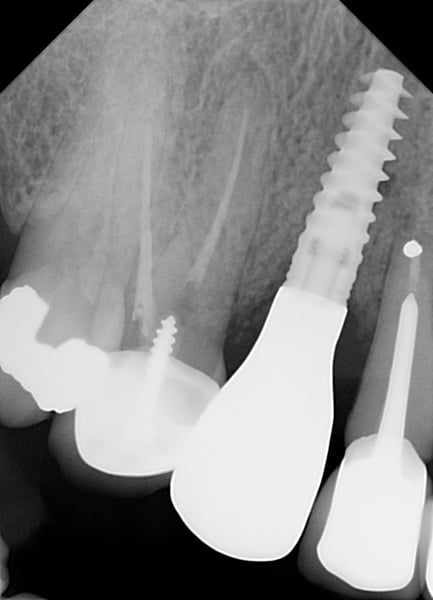

Following a GBR at the time of implant placement (Pictures 1,2,3), a buccal ridge deficiency persisted (Picture 4). Surgical uncovery of the implant to expose the cover screw revealed successful bone regeneration around the implant, but a residual lack of ridge contour (Picture 5).

Instead of using a traditional particulate graft covered with a resorbable membrane, a “flexible bone graft” sheet, DALI Flex Graft, was placed over the buccal plate to augment the buccal contour (Pictures 6 & 7). Because the graft comes hydrated, it is easy to handle and adapt to the defect location. The flap was then pulled over the graft and adapted around the healing abutment (Picture 8).

This a follow up to our original case using the DALI Flex Graft, a 1 mm thick demineralized cortical allograft that when hydrated, becomes flexible and easily adapts to graft sites. For reference, the original case is here: DALI Flex Graft for Buccal Augmentation